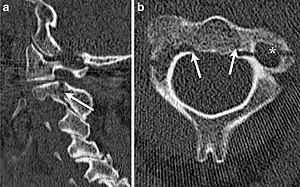

Hangman's fracture is the colloquial name given to a fracture of both pedicles, or partes interarticulares, of the axis vertebra (C2).[1]

| CT scan of hangman's fracture | |

The mechanism of the injury is forcible hyperextension of the head, usually with distraction of the neck. Traditionally this would occur during judicial hanging, when the noose was placed below the condemned subject's chin. When the subject was dropped, the head would be forced into hyperextension by the full weight of the body, a sufficient force to cause the fracture. However, despite its long association with judicial hangings, one study of a series of such hangings showed that only a small minority of hangings produced a hangman's fracture.[5]

Although a hangman's fracture is unstable, survival from this fracture is relatively common, as the fracture itself tends to expand the spinal canal at the C2 level. It is not unusual for patients to walk in for treatment and have such a fracture discovered on X-rays. Only if the force of the injury is severe enough that the vertebral body of C2 is severely subluxed from C3 does the spinal cord become crushed, usually between the vertebral body of C3 and the posterior elements of C1 and C2.